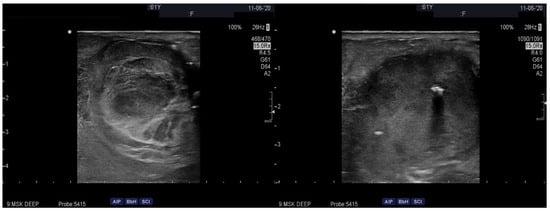

2. Case Presentation